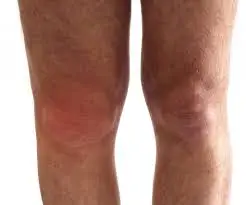

Lututnya terasa tegang, dan setiap langkah disertai rasa tidak selesa, kadang-kadang berdenyut tanpa sebab yang jelas. Baru tadi semuanya normal, tapi sekarang, lutut sebelah kanan kelihatan lebih besar dan makin membesar.

Dia menekan perlahan di sekitar sendi. Ada bahagian yang lembut, dan terasa seperti belon air dalam lututnya. Degupan jantungnya mula laju. Tiada insiden jatuh atau cedera berlaku padanya. Mengapa lututnya tiba-tiba jadi begini?

Lutut bengkak adalah satu masalah kesihatan pada lutut yang menyebabkan terkumpulnya air radang (knee effusion) di dalam lutut secara berlebihan menyebabkan lutut kelihatan besar dan sukar untuk berjalan serta sakit lutut.

Ia terjadi akibat radang atau inflamasi. Kebanyakan orang mengalami kesan ini akibat kecederaan, obesiti, atau jangkitan kuman. Kebiasaannya, hanya salah satu lutut saja yang akan terjejas dengan masalah ini.